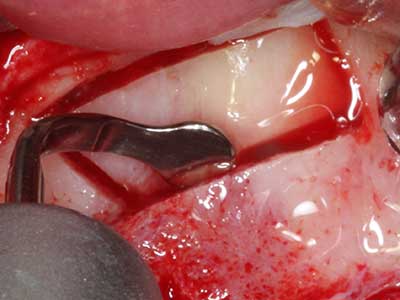

Si es preciso realizar intervenciones quirúrgicas en las que el hueso está en contacto directo con estructuras sensibles, como son los vasos sanguíneos o los nervios, los instrumentos rotativos presentan un enorme potencial de provocar lesiones iatrogénicas. Así, precisamente en la representación de nervios después de una lesión iatrogénica, o en el transcurso de la lateralización de un nervio para resecciones, reconstrucciones o incorporación de implantes, los equipos piezoeléctricos pueden resultar muy útiles para preparar la tapa ósea y retirar las partes de tejido duro cercanas al nervio (fig. 17-20). Por lo general, un ligero contacto del cordón nervioso con el inserto piezoeléctrico no tiene consecuencia alguna; ahora bien, un procedimiento poco cuidadoso con movimientos tipo sierra o piezas de trabajo sobre la base ósea aún existente puede provocar lesiones nerviosas temporales o incluso permanentes. Con todo, el riesgo de sufrir una lesión de este tipo se considera significativamente inferior que en los casos en los que se utilizan sierras y fresas (Pereira, Gealh et al. 2014).